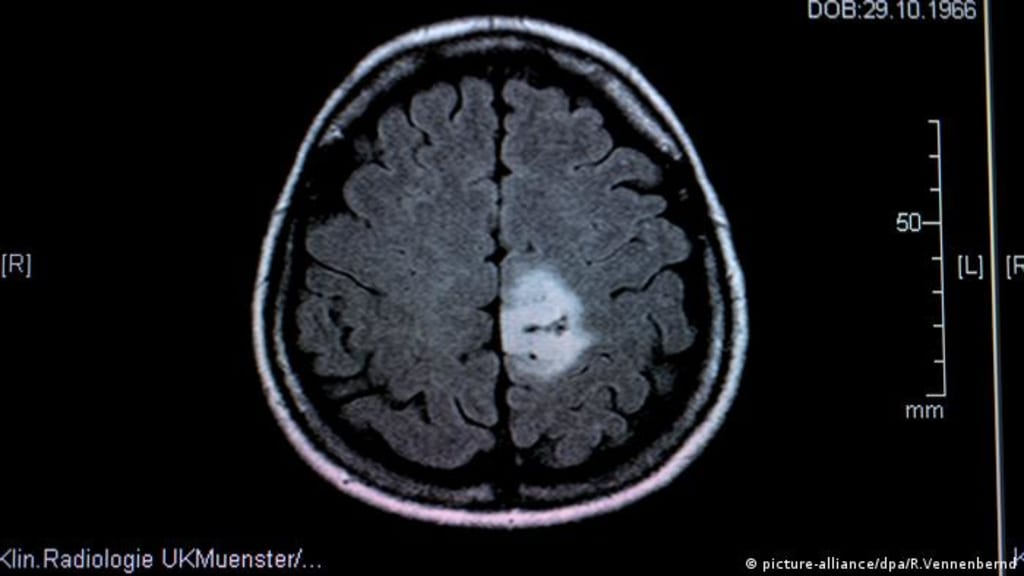

A brain tumour is a mass of abnormal cells growing in the brain. The cells can come from the brain itself or from its lining (primary brain tumours) or from other places in the body (secondary or metastatic brain tumours). Primary brain tumours can be benign or malignant. Secondary brain tumours are always malignant.

Size doesn’t matter… this is true. The size of a brain tumour doesn’t matter nearly so much as where it is located. A large, benign tumour may be easily accessible and therefore easy to remove. Or you can have a pea –sized tumour that is critically placed, and so makes treatment very difficult. However, treatments options are developing all the time and one size doesn’t fit all. Some small tumours, in tricky locations, may be treated by radiosurgery and some large, diffuse tumours crossing the midline of the brain can be difficult to treat with radiation. So each case needs to be reviewed, discussed and options explored. It’s complex!